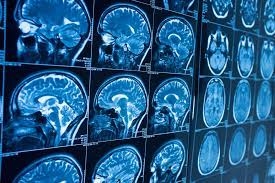

| Dư luận Canada đang xôn xao bởi căn bệnh não lạ. (Nguồn: NY Post) |

RT đưa tin, một căn bệnh não bí ẩn có tên là "Hội chứng New Brunswick" hiện đang trở thành chủ đề được quan tâm tại Canada, sau khi hàng chục người đã mắc và 6 người tử vong trong thời gian qua.

Căn bệnh được đặt tên dựa theo tỉnh New Brunswick, nơi căn bệnh lạ xuất hiện và làm ít nhất 48 người, từ độ tuổi 18 tới 85, mắc bệnh. Số lượng bệnh nhân nam/nữ là tương đương nhau. Người bệnh bị suy kiệt sức khỏe nhanh chóng, bị gặp ảo giác thị giác và thính giác, mất trí nhớ, đi lại khó khăn và gặp các vấn đề về giữ thăng bằng.